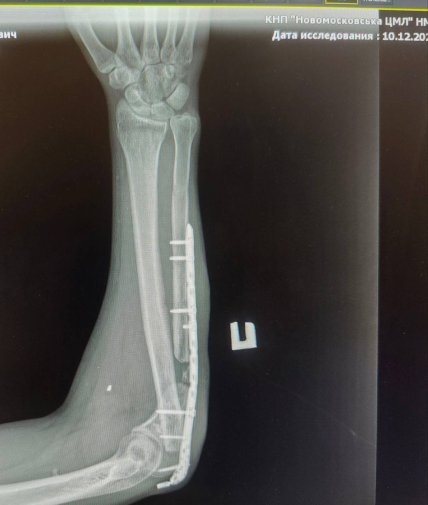

На це ветеран відповів йому лайкою. Після цього правоохоронці поклали його на асфальт та заламали руки. При цьому вони не відреагували на крики та пояснення, що в руці знаходиться металева пластина.